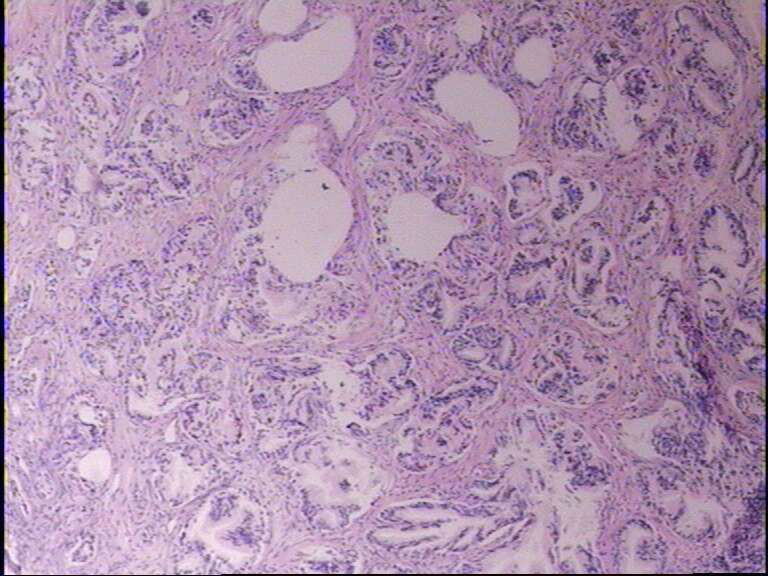

男72岁,排尿困难一年

• 前列腺图2

图2

前列腺良性增生,最好做P5O4S 、P63 、34βE12

良性前列腺增生症。

结节性增生

符合前列腺良性增生